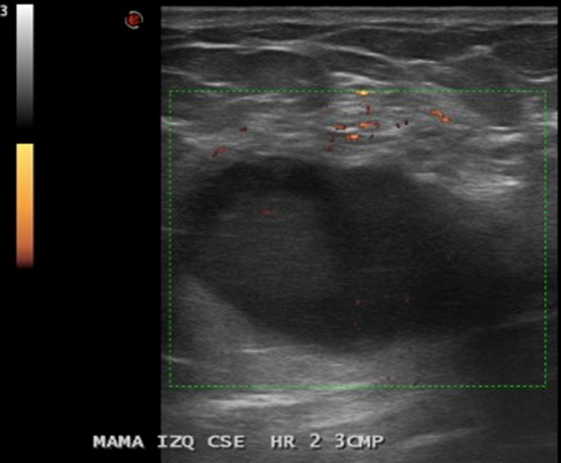

En Mama IZQ CSE HR 2, a 3 CMP, imagen nodular hipoecogénica, ovalada, 31 x 36 x 26 mm.

• La mama izquierda presenta en el cuadrante supero-externo, eje horario 2, a 3 cm. del pezón, imagen nodular hipoecogénica, bien definida, ovalada de 36 x 26 x 31 mm., sugerente de lesión quística con contenido, no vascularizado. Esta lesión presenta escaso refuerzo acústico posterior.

Impresión: Lesión sugerente de quiste con contenido en mama izquierda, se recomienda control evolutivo. BIRADS US 3.